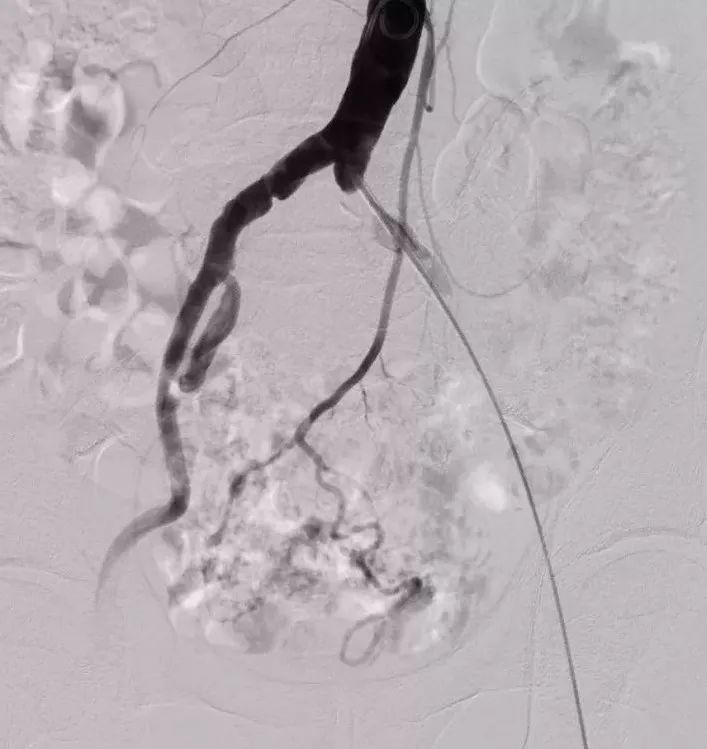

对于不少的血管性疾病,如动脉硬化性闭塞、动静脉畸形、静脉血栓形成等,由于病情复杂,或因为是全身性疾病,或未能良好控制其基础疾病等原因,都可能需要反复多次进行介入治疗。

动脉硬化性闭塞症是全身性疾病,不必也不能一次性解决全部问题,适时地解决当前的突出问题即可,如果后续其